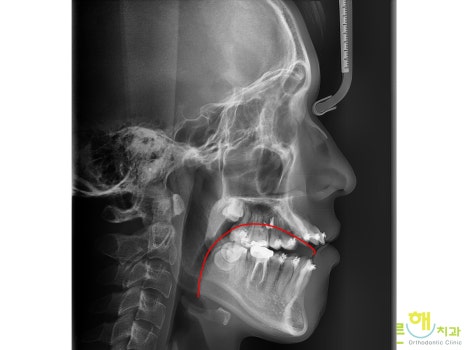

±³ÇÕÀÌ ¾ÈÁ¤µÇ¸é¼­

¾ó±¼±æÀ̰¡

´Ù¼Ò ª¾ÆÁö°í

±³ÇÕÀÌ °³¼±µÇ¸é¼­

ÁÂ¿ì ´ëμºÀÌ °³¼±µÈ °ÍÀ» º¼ ¼ö ÀÖ½À´Ï´Ù.

¾ó±¼ Á¤¸é¿¡¼­ ºÃÀ» ¶§µµ

¾È¸éºñ´ëĪÀÌ ¸¹ÀÌ °³¼±µÈ °ÍÀ»

º¼ ¼ö ÀÖ½À´Ï´Ù.